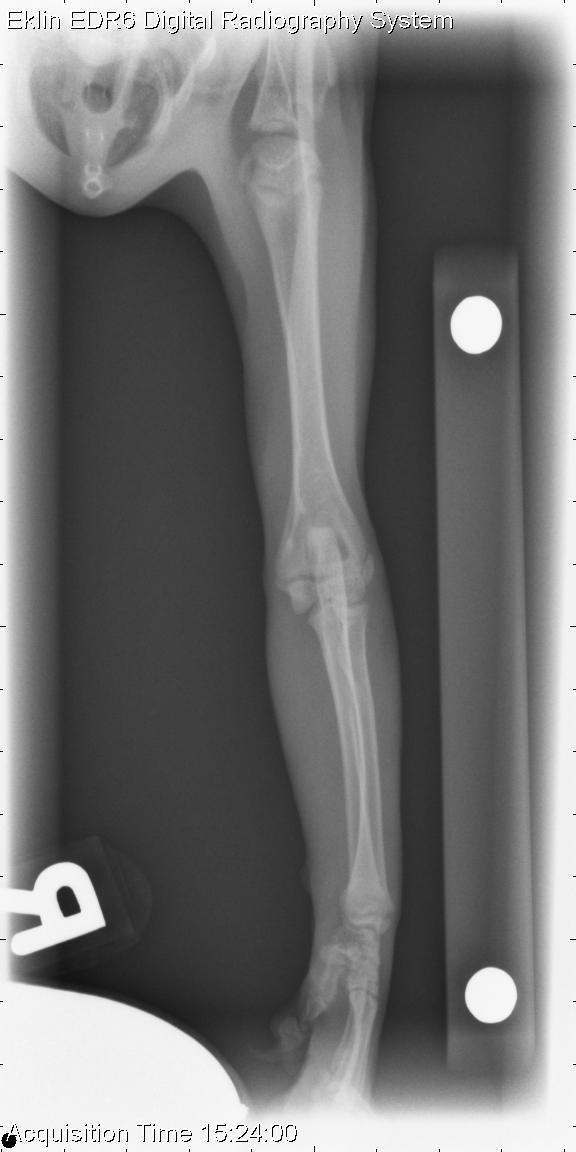

Today’s case is an orthopedic one involving a 3 month old domestic short haired cat with acute onset of left forelimb lameness. Check it out, and post your interpretations in the comments section.

R LAT Elbow

There is a type 3 Salter-Harris fracture through the lateral distal humeral physis with mild cranial displacement of the humeral condyle in relation to the proximal humeral fracture fragment. There is moderate soft tissue swelling surrounding the distal aspect of the left humerus.